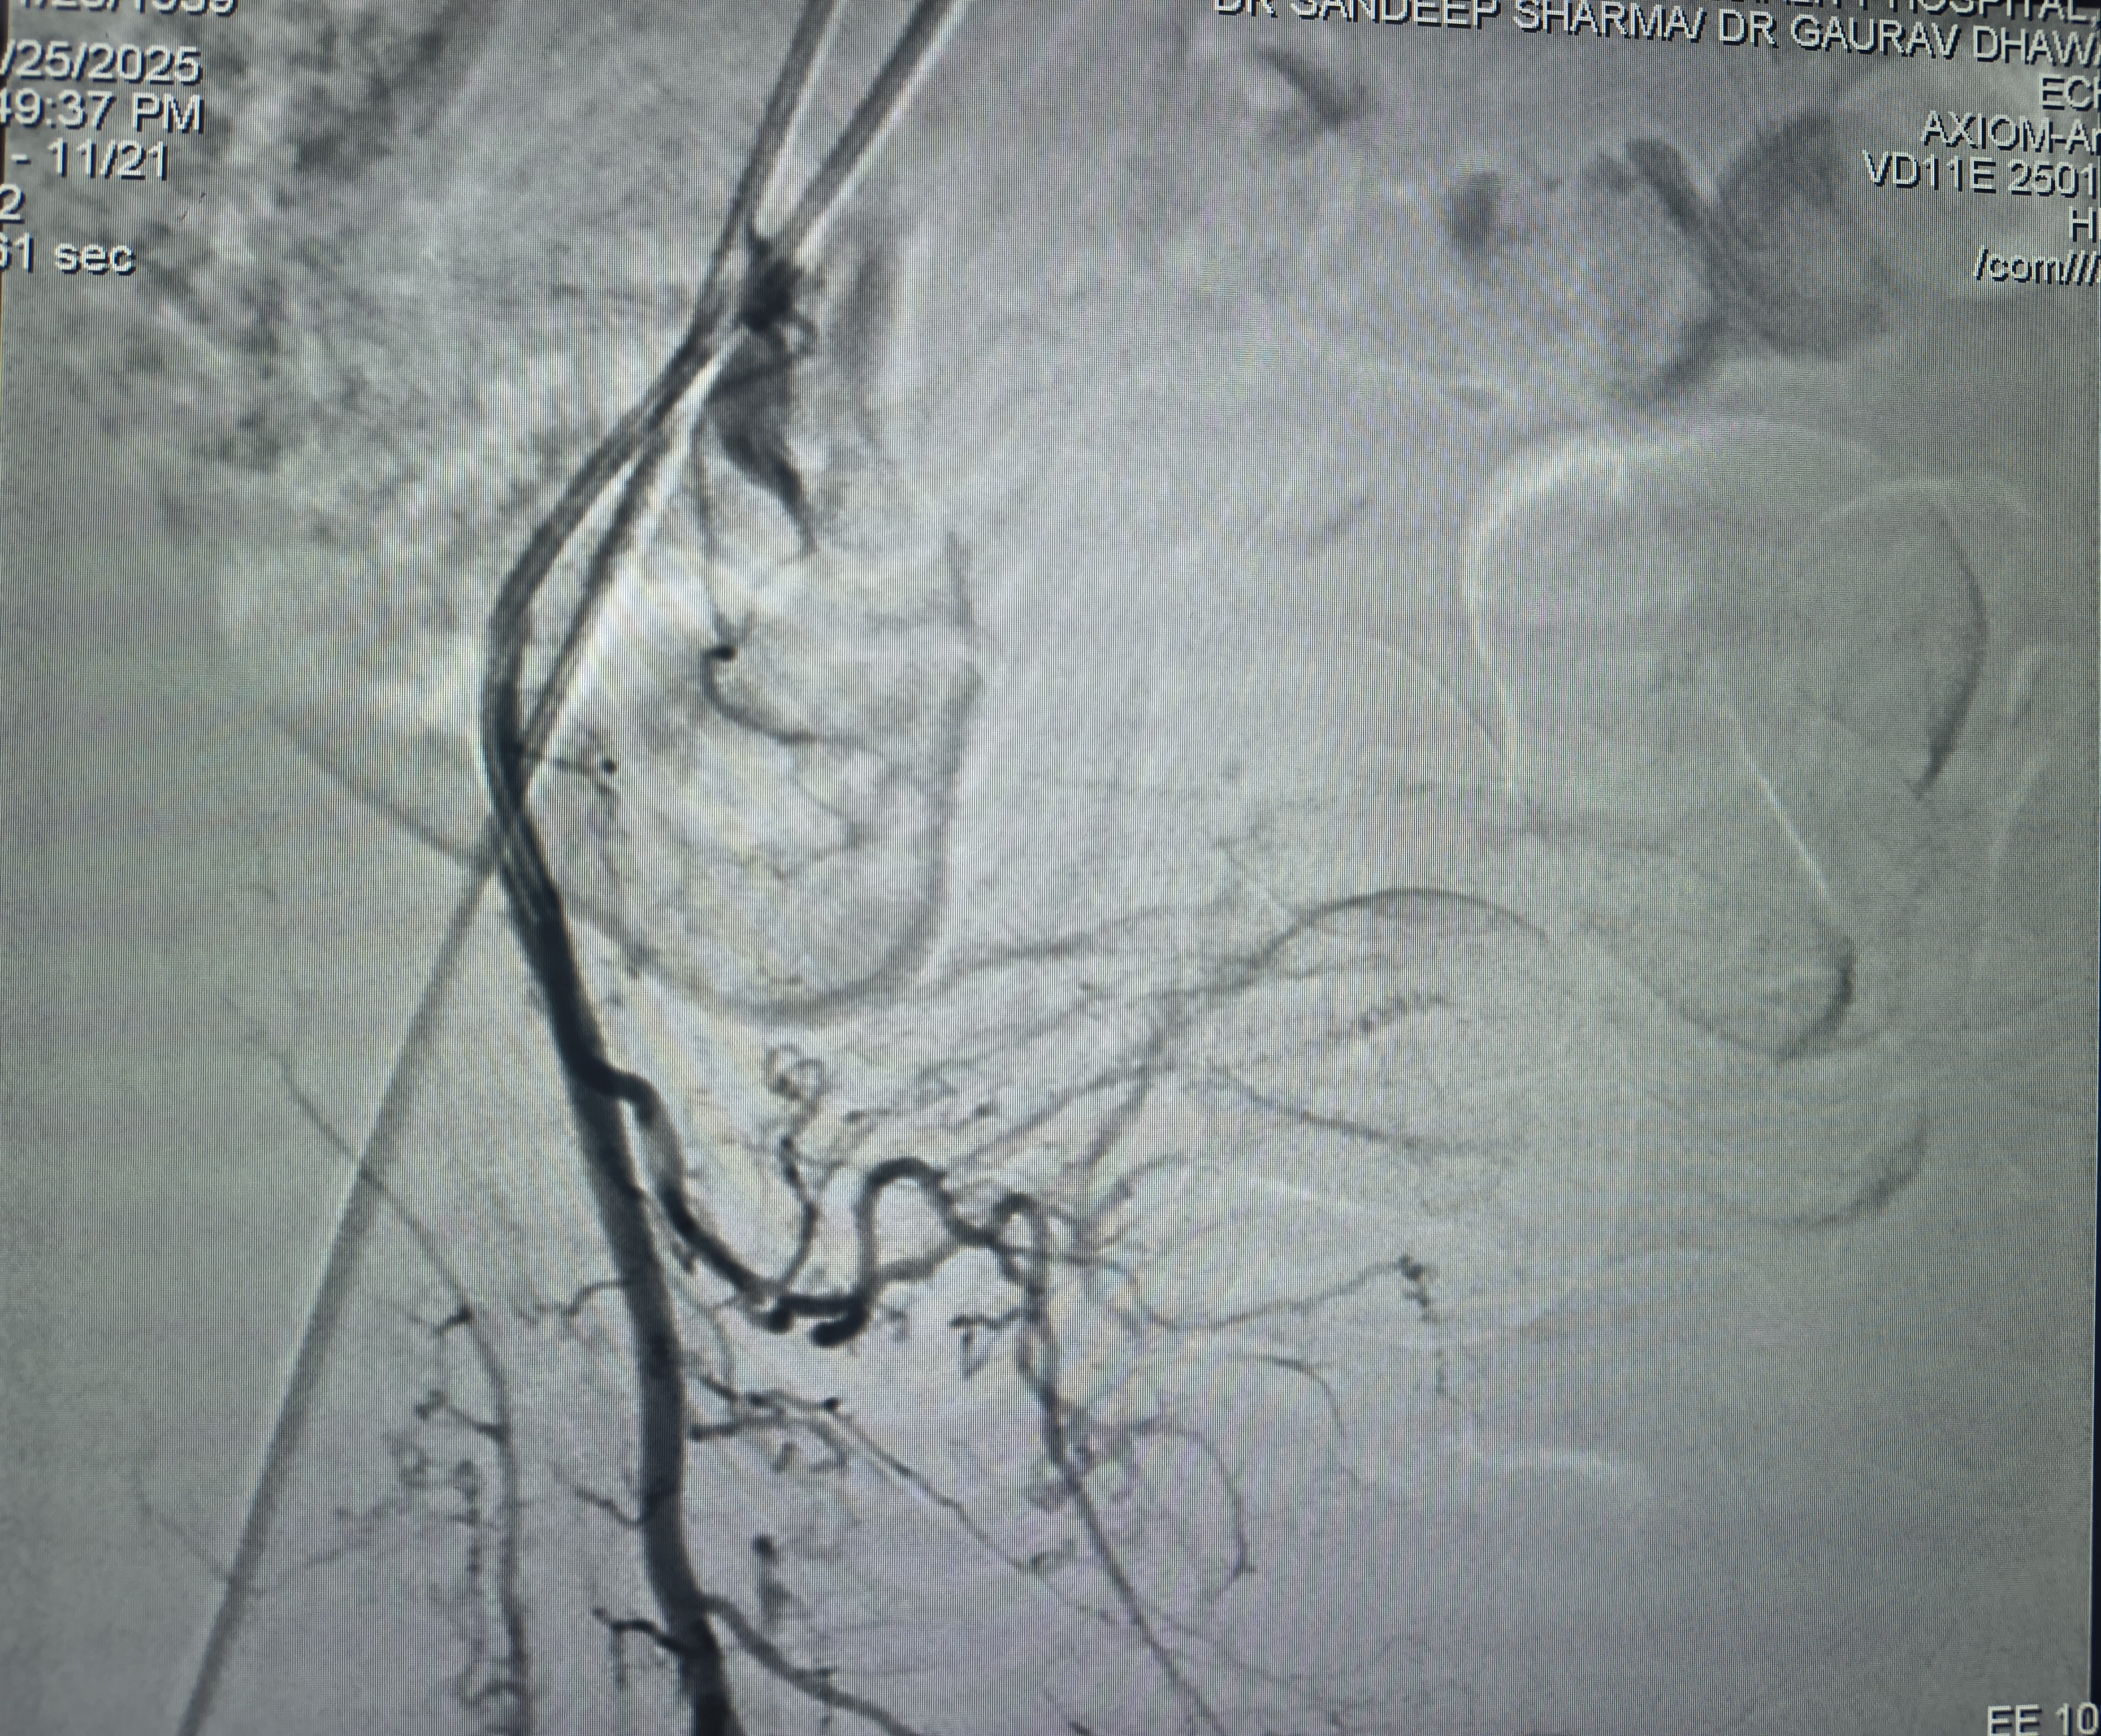

Prostate Artery Embolization

Prostate Artery Embolization: How Colonel Madhupreet Singh Found Relief at IRfacilities